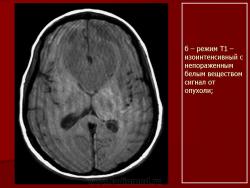

Лимфомы головного мозга.

1.Uv_.Slayd48.JPG2.Uv_.Slayd49.JPG3.Uv_.Slayd50.JPG4.Uv_.Slayd51.JPG5.Uv_.Slayd52.JPG6.Uv_.Slayd53.JPG7.Uv_.Slayd54.JPG8.Uv_.Slayd55.JPG9.Uv_.Slayd56.JPG10._Uv.Slayd57.JPG11.Uv_.Slayd58.JPG